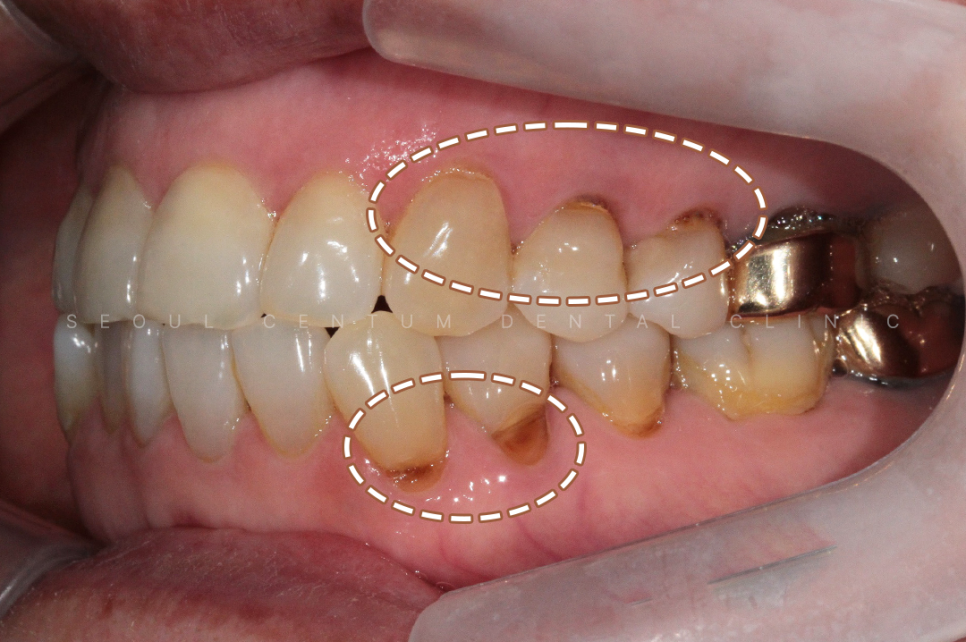

아래 사진은 실제 서울센텀치과에

치경부마모증이 뭔지 모르는 상태로

내원하셔서 치료를 하게 된 케이스인데요.

60대 여성으로 동네에 치과에 스케일링을

오랫만에 하러 갔다가

치아가 파였다는 말을 듣고

거울을 보고나니 치아가 보기 싫어져서

라는 이유로 내원을 하셨어요.

실제 육안으로 봤을 때도 크게

치경부마모증이 진행된 부분이 많았고

당일에 바로 진행을 하게 되었습니다.

크게 진행이 된 8개의 치아를 진행하기로 했고

강도가 강한 레진으로 진행해 오래

유지를 잘 해보시기로 이야기가 되어

레진으로 진행을 했습니다.